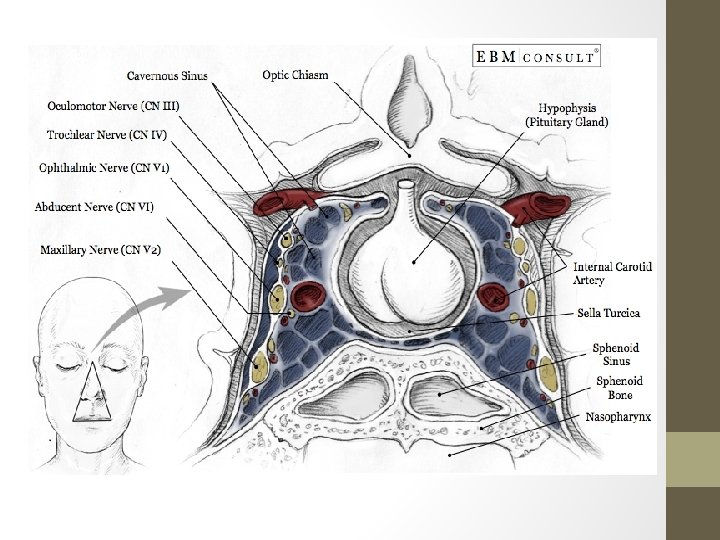

Cavernous Sinuses Located on either side of the pituitary fossa and body of the sphenoid bone between the endosteal and meningeal layers of the dura. (lateral and superior to the sphenoid sinus and are immediately posterior to the optic chiasm) • Boundaries: Roof: fold of dura mater attached to the anterior and middle clinoid processes Anterior wall: medial end of the superior orbital fissure Posterior: petrous apex Medial: endosteum of body of the sphenoid bone Lateral: dura mater from the ridge of the roof to the floor of the middle cranial fossa Floor: greater wing of sphenoid bone

Cavernous Sinus • Receive venous blood from the facial veins (via the superior and inferior ophthalmic veins) as well as the sphenoid and middle cerebral veins(-inferior &superior petrosal sinusessigmoid-ijv) • Because of this complex is made of valveless veins, blood can flow in any direction depending on the prevailing pressure gradients. Since the cavernous sinuses receive blood via this distribution, infections of the face including the nose, tonsils, and orbits can spread easily by this route.

Cavernous Sinus